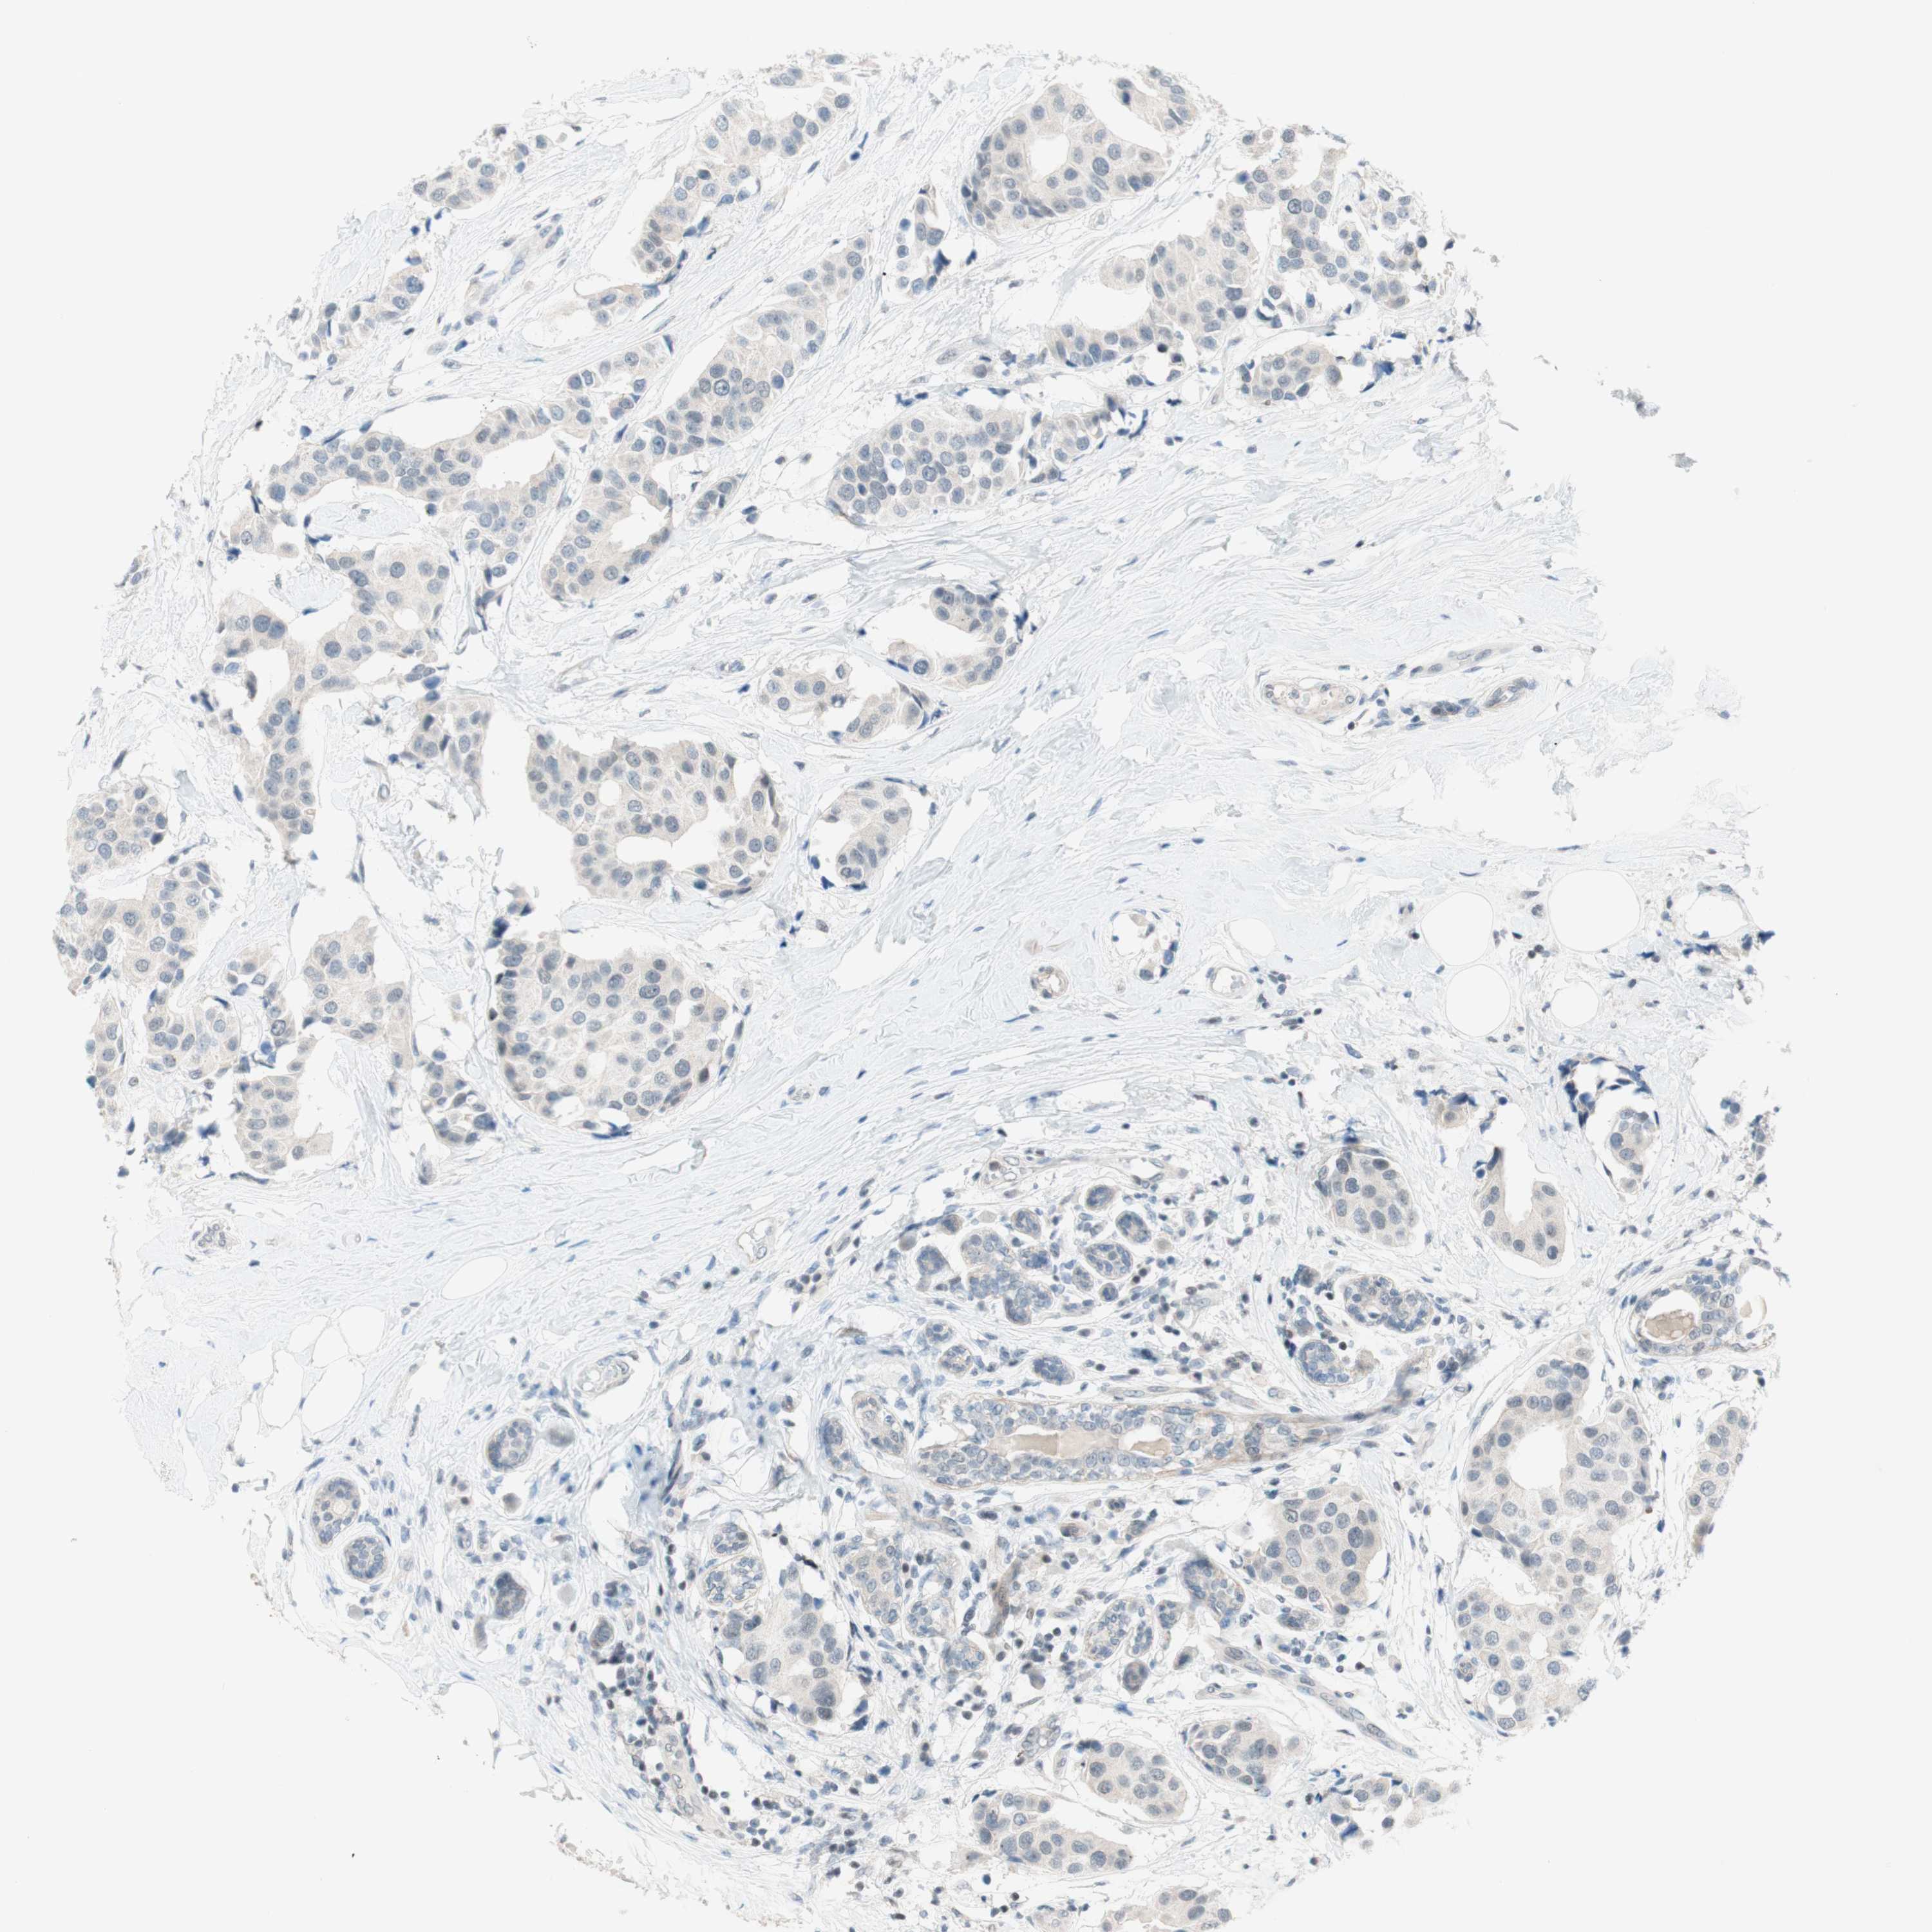

CANCER BREAST CANCER Show tissue menu

BRCA TCGA BRCA VALIDATION PROTEIN EXPRESSION

ANTIBODIES